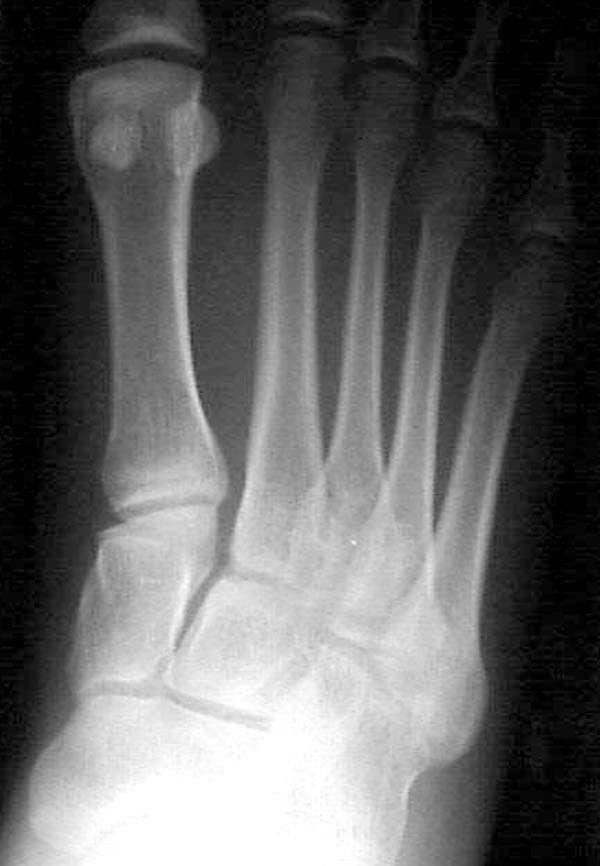

Здесь КТ и сравнительные снимки стопы под нагрузкой.

Диагностировано повреждение медиальной и латеральной колонны.

По снимкам нельзя исключить разрыв связки Лисфранка (связки между медиальной клиновидной костью и основанием второй плюсневой). Помогает в диагностике клиника (наличие изолированной гематомы на подошвенной поверхности стопы) и МРТ картина. Если связка повреждена - необходимо оперативное лечение.